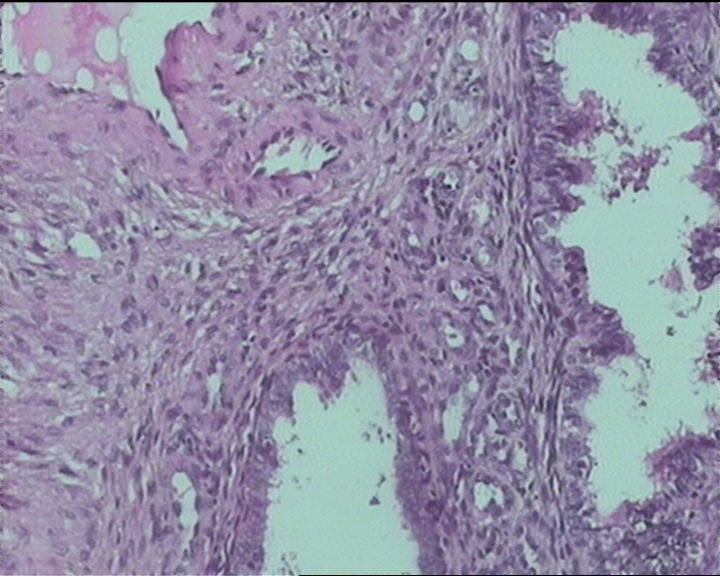

54岁女性,临床“宫颈息肉”送检;巨检:组织一块1。5*1CM,灰红。

Sternberg病理学上诊断宫颈原位腺癌的标准是腺体的上皮去粘液分化,呈乳头状或筛网状增生,核分裂易见,这例显然达不到此标准。此例还是归入到腺上皮不典型增生为好。

It is benign. Benign endocervical polyp with tubal metaplasia.

输卵管粘膜化生

细胞及腺体均有异形,图6、11、16象有纤维间质反应,考虑高级别上皮内瘤变/原位癌,腺癌不能除外。